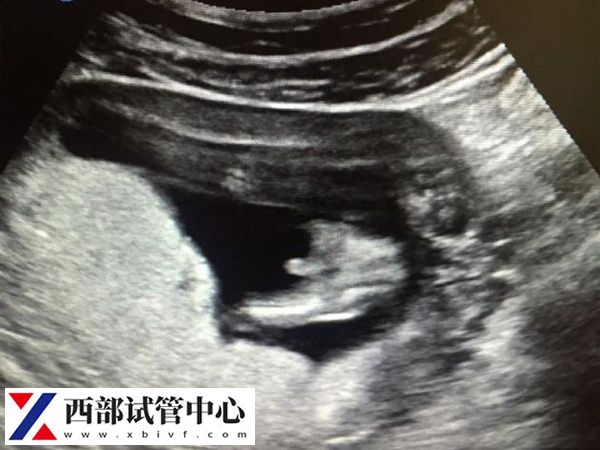

第三次超声检查

三超在怀孕11~13周左右做,也就是我们常说的NT检查,NT检查可以早期发现染色体性疾病、心血管异常等,其中以21三体综合征最为常见,它的发生率随着孕妇年龄的增长而有所升高。若是有就需要及时终止妊娠,若是没有就需要及时按医生规定去医院产检。